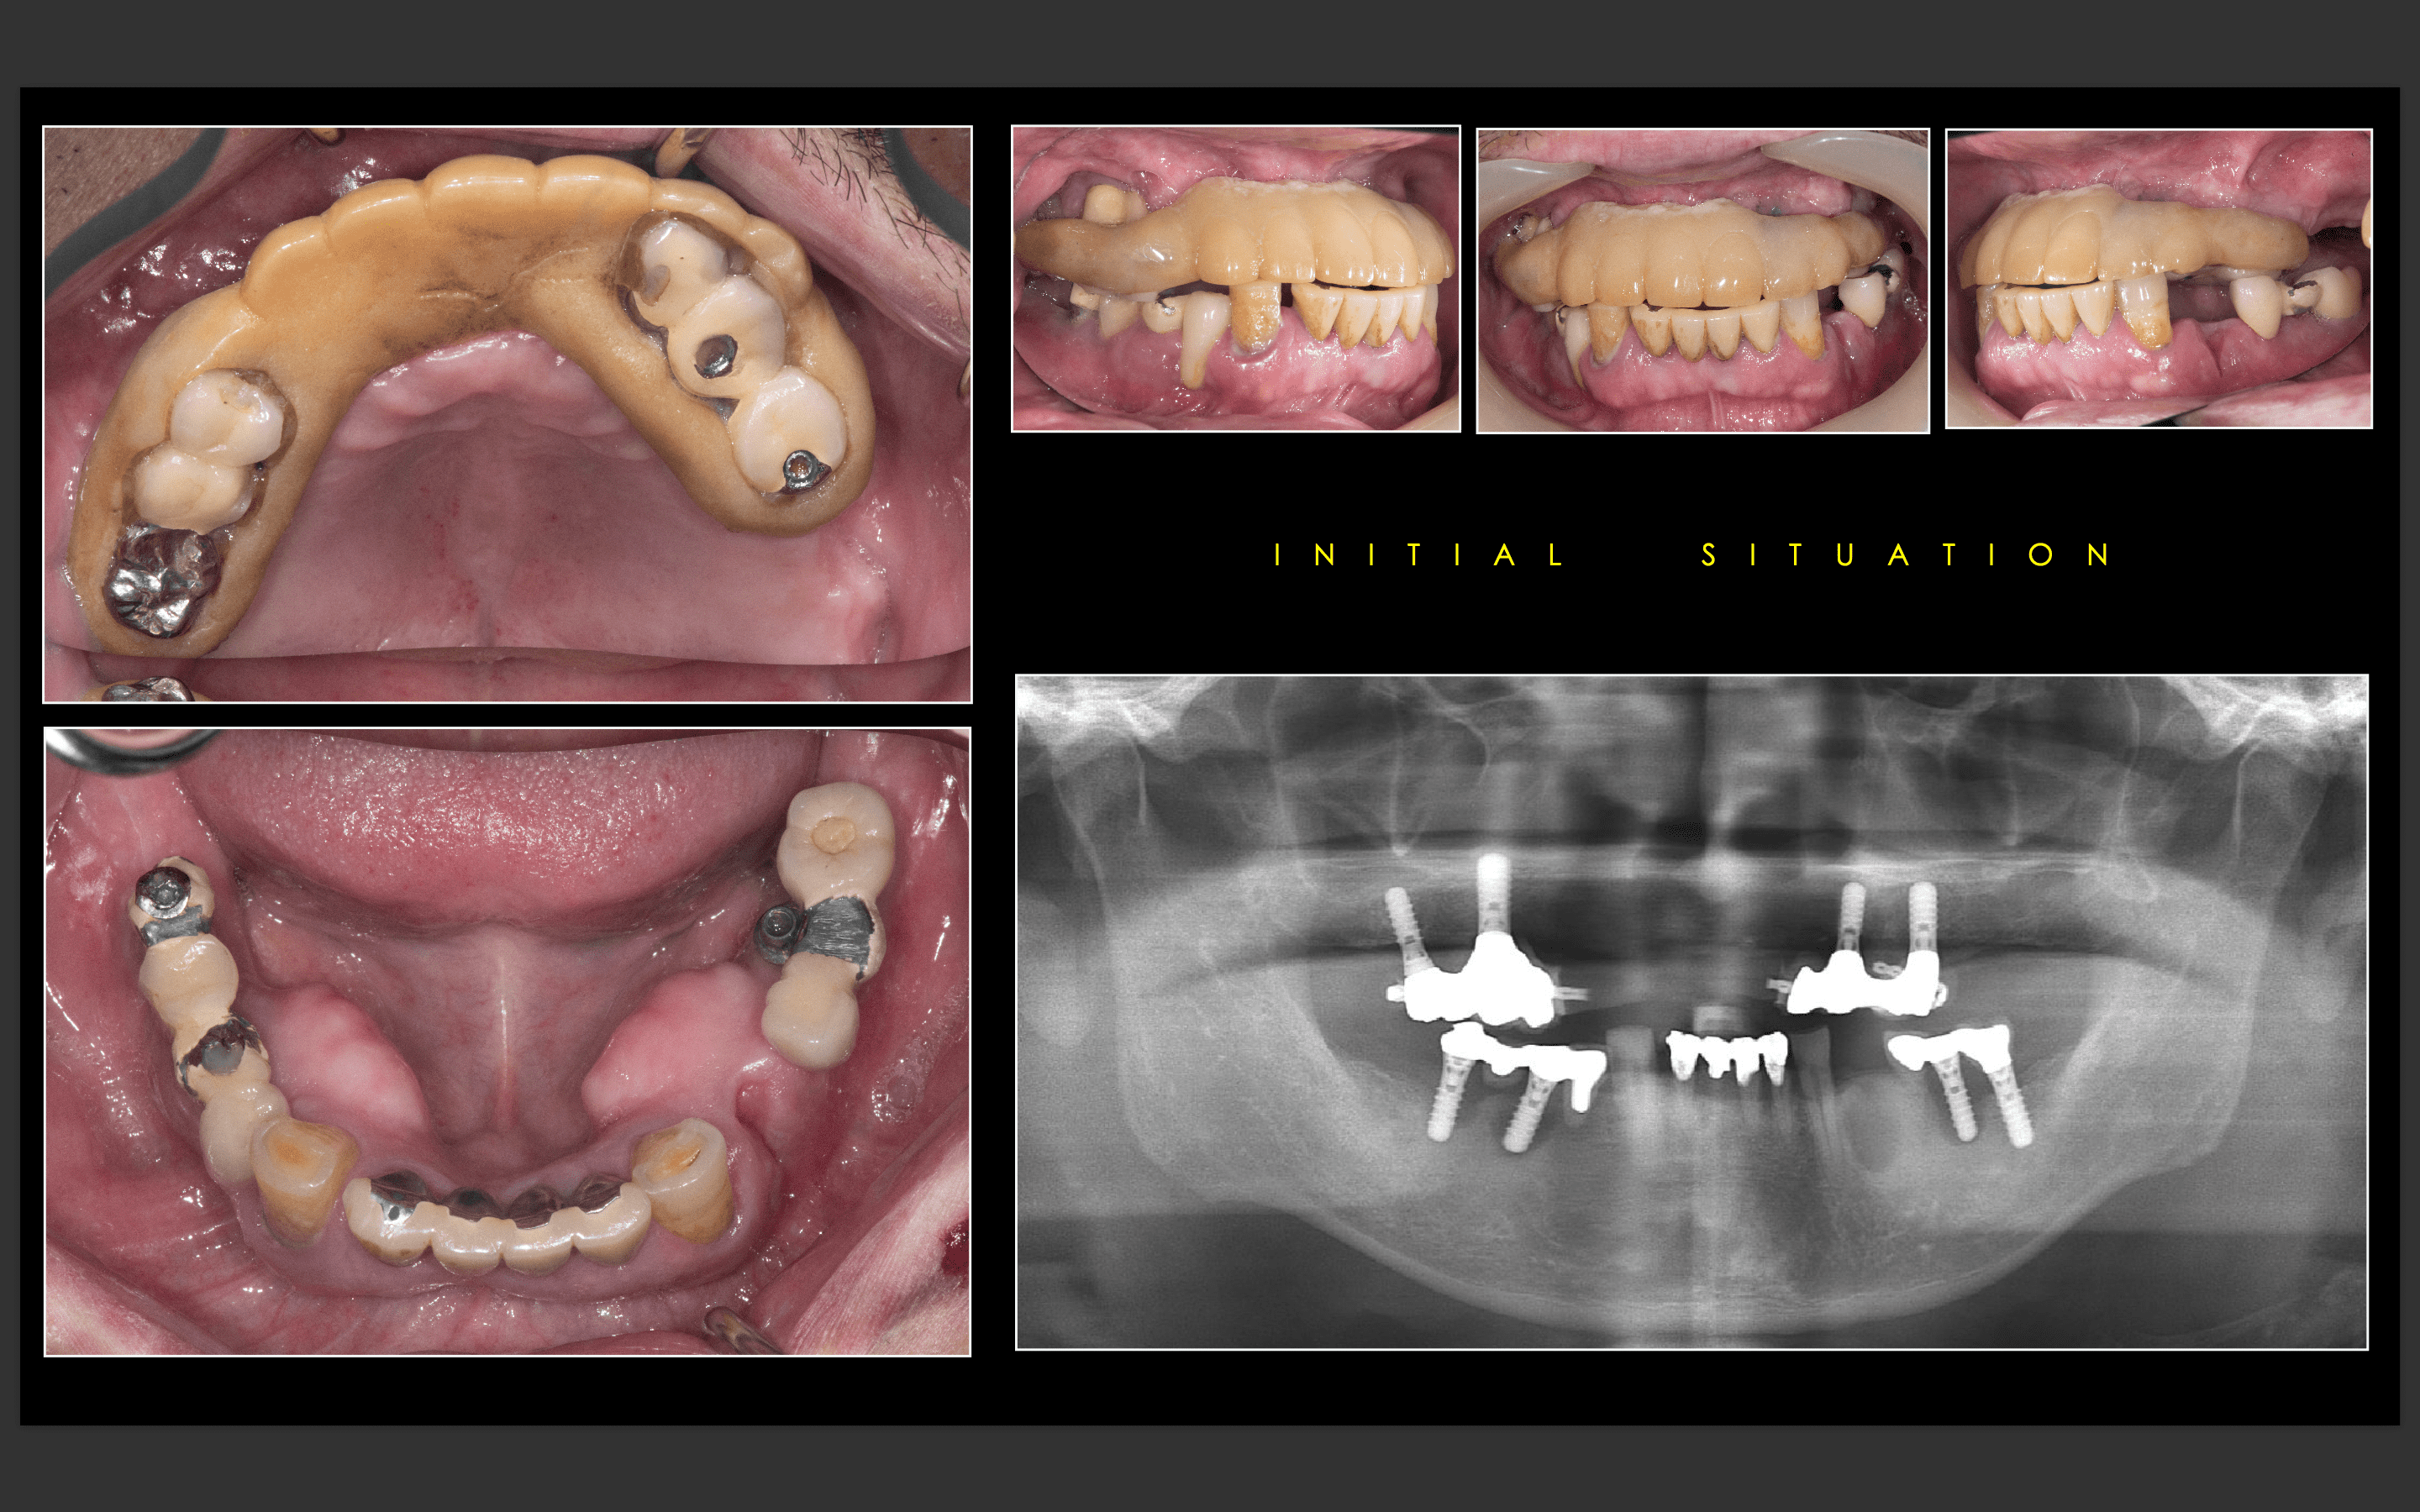

術前写真

上顎:虫歯がひどく、保存不可能な状態である。

下顎:インプラントが入っているが、被せ物がなずれたまま放置になっている。

パノラマX線

上顎:根の病気と虫歯で保存不可のな状態。

下顎:インプラントが不適切な位置に入っており、撤去が必要な状態。